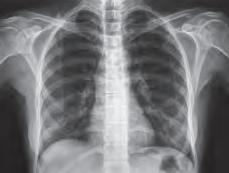

CNRI/SCE

Tricomoníase

A tricomoníase é causada pelo protozoário Trichomonas vaginalis Nas mulheres, os principais sintomas são o corrimento vaginal e a ardência ao urinar, e nos homens é o corrimento pela uretra. Em geral, muitos homens são portadores assintomáticos, ou seja, não apresentam sintomas da infecção. O tratamento é feito por meio de medicamentos específicos prescritos pelo médico. As pessoas infectadas devem evitar relações sexuais até que estejam completamente curadas. A prevenção é evitar o contato sexual com pessoas contaminadas e fazer uso do preservativo nas relações sexuais.

Protozoário Trichomonas vaginalis. Microscopia eletrônica; colorida artificialmente. Imagem ampliada em 7 mil vezes (quando aplicada com 9 cm de largura).